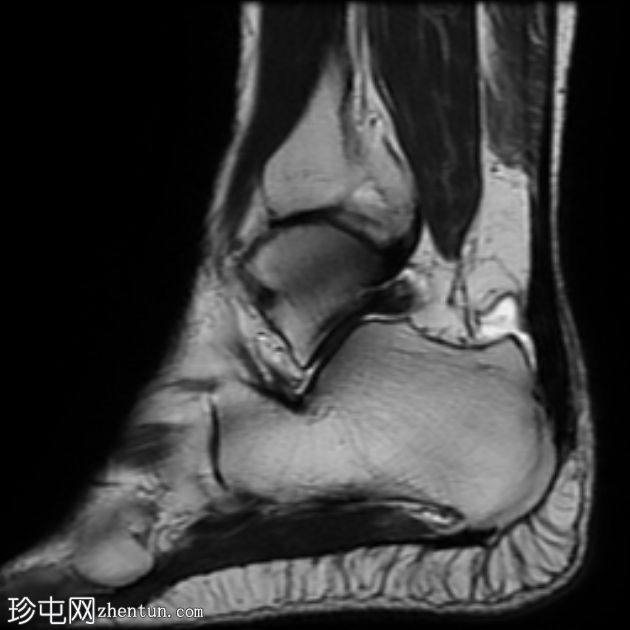

矢状位

T2

跟腱插入

,伴有跟腱明显增厚,可诱发异常信号、跟腱后滑囊炎、跟骨后突及骨髓水肿信号。

Haglund综合征的检查结果令人印象深刻。

Haglund综合征是指以下三联征(Haglund三联征):

跟腱插入性病

跟腱后滑囊炎

Haglund畸形(即跟骨后上外生骨疣)